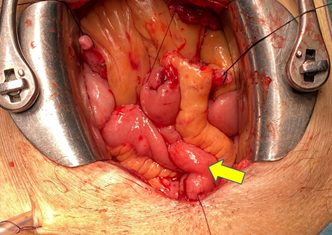

Bệnh nhân T. có tiền sử mổ sỏi bàng quang cách đây 6 năm, mổ nội soi cắt u xơ tiền liệt tuyến cách đây 1 năm. Lần này nhập viện với lý do đái máu tươi toàn bãi, thỉnh thoảng có máu cục, kèm theo triệu chứng tiểu khó, tia tiểu yếu. Qua thăm khám lâm sàng và hình ảnh chụp CT. Scanner cũng như hình ảnh soi bàng quang cho thấy người bệnh có một khối u kích thước 3x4 cm ngay lỗ niệu quản trái, đụng vào dễ chảy máu. Thực hiện cắt mẫu làm giải phẫu bệnh cho kết quả carcinoma niệu mạc, biệt hóa kém, đã xâm lấn lớp cơ bàng quang. Sau khi tiến hành hội chẩn, bệnh nhân được chỉ định phẫu thuật cắt bàng quang toàn bộ.

Hình ảnh u bàng quang của người bệnh trên phim CT.Scanner